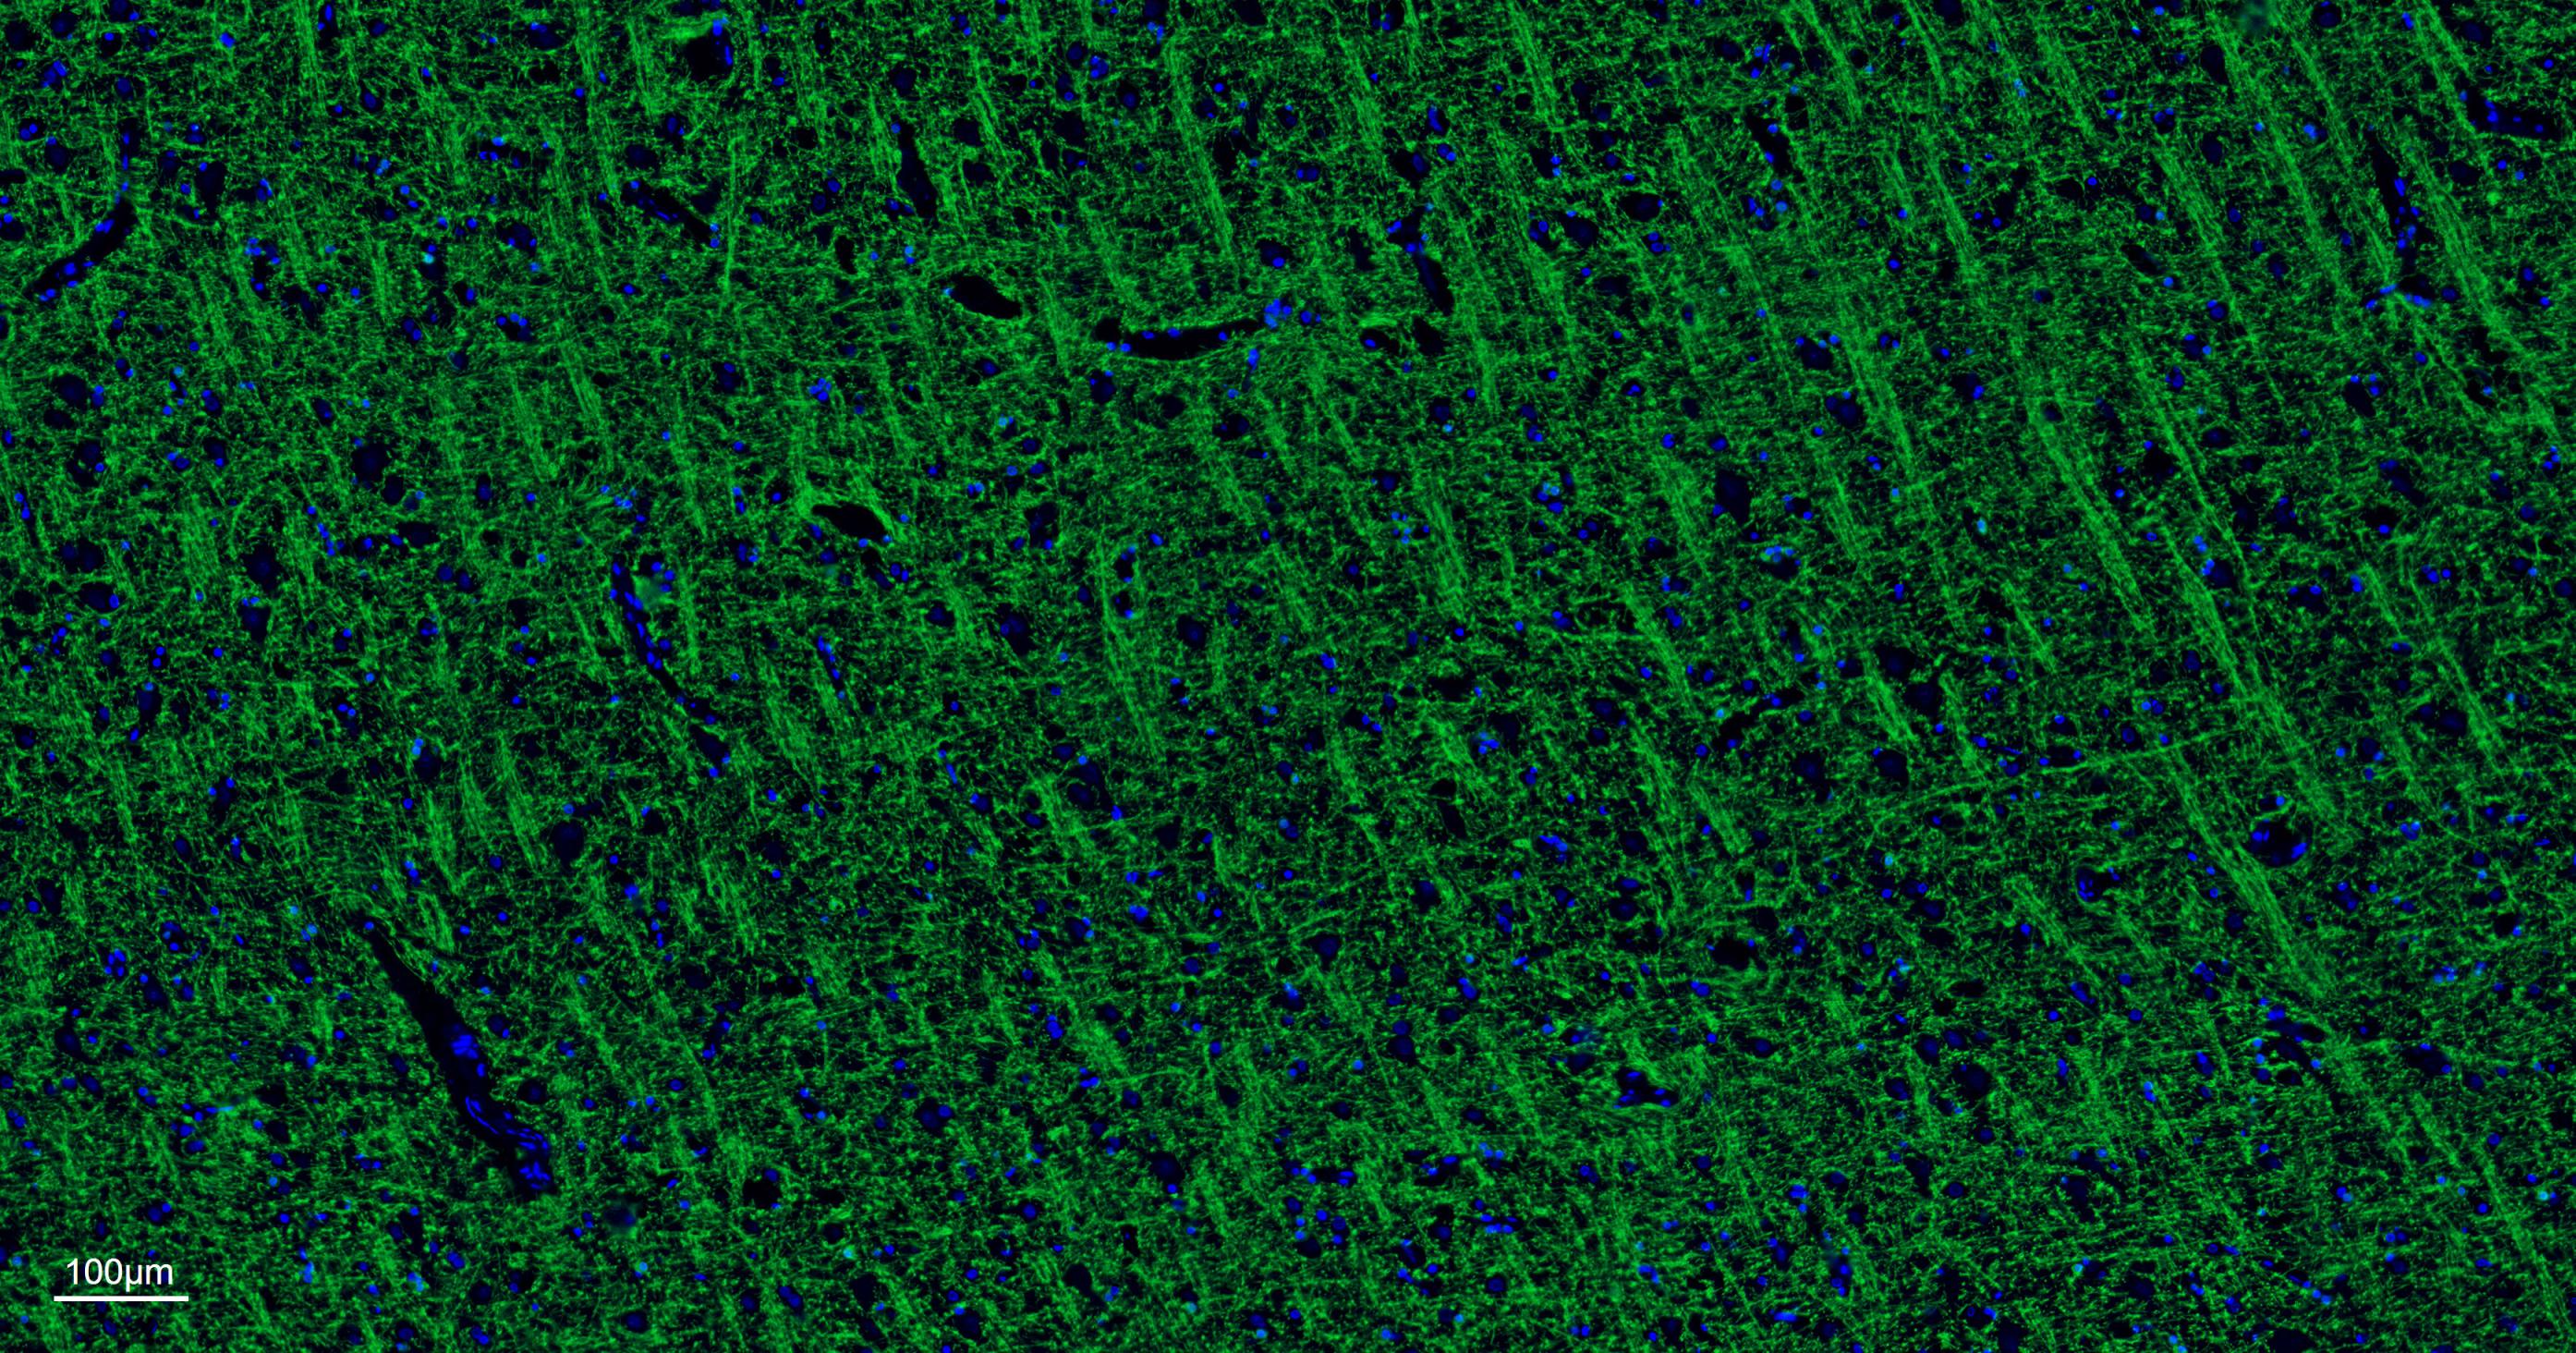

The protein encoded by the classic MBP gene is a major constituent of the myelin sheath of oligodendrocytes and Schwann cells in the nervous system. However, MBP-related transcripts are also present in the bone marrow and the immune system. These mRNAs arise from the long MBP gene (otherwise called "Golli-MBP") that contains 3 additional exons located upstream of the classic MBP exons. Alternative splicing from the Golli and the MBP transcription start sites gives rise to 2 sets of MBP-related transcripts and gene products. The Golli mRNAs contain 3 exons unique to Golli-MBP, spliced in-frame to 1 or more MBP exons. They encode hybrid proteins that have N-terminal Golli aa sequence linked to MBP aa sequence. The second family of transcripts contain only MBP exons and produce the well characterized myelin basic proteins. This complex gene structure is conserved among species suggesting that the MBP transcription unit is an integral part of the Golli transcription unit and that this arrangement is important for the function and/or regulation of these genes.

| IF | Human, Mouse, Rat | 1:200-1000 |